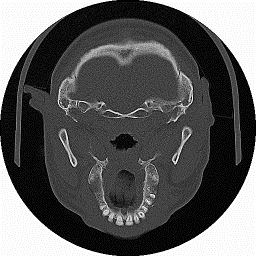

In figura 1‑8 si mostra il caso frequente di un paziente sottoposto a TAC , la cui immagini contiene anomalie dovute alla presenza di amalgami dentali.

Figura 18 Immagine originale e regione d’interesse